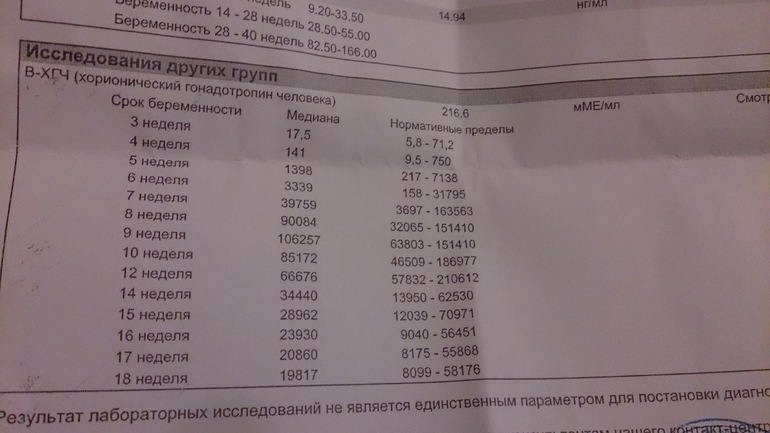

Акушерские недели беременности: особенности и расчёт сроков

Раздел: Идеи и советы